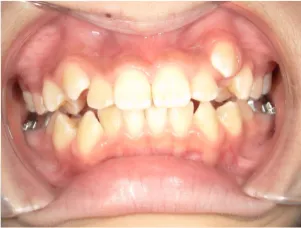

治療中➁小6:QH・BHでアーチ形態改善・上顎前歯を並べる

| 行ったご提案・診断内容 | 生え変わりが終わってなくマルチブラケット法による咬合治療には早い時期のため、顔立ちの成長を促す目的で歯列弓(アーチ)の拡大と前歯を並べながら永久歯が生えるのを待ち、咬合治療開始時に再診断で抜歯、非抜歯を最終検討する提案をしました。 再診断時(写真②)、歯列の拡大と上顎前歯の並べ替えはされていましたが八重歯となったため抜歯、非抜歯を検討しました。 口元は特に問題がなく非抜歯で八重歯を改善するためのスペースを作ることが可能なため非抜歯治療を提案しました。 治療は、 ・拡大および上顎左右6を遠心移動させてスペースを作る 予定装置 |